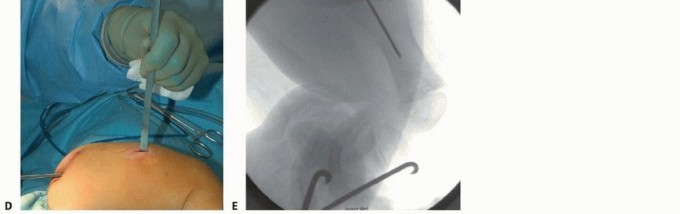

## To measure the length of the female rod intraoperatively, it is placed with the threaded portion just at the top of the ossified greater trochanter with C-arm verification using a metal marking device distally approximately 1 cm above the physis (TECH FIG 3A).

## The female nail is covered with K-Y Jelly (Johnson & Johnson, New Brunswick, NJ), then cut with a diamond-tip burr and cooled with sterile saline.

## The cannulated portion must be checked to ensure that no metal will impinge on the male nail to prevent it from lengthening and that any metal shards are rinsed off (TECH FIG 3B,C).

## A circular saw and rod holder are also available from the manufacturer to cut the female rod (TECH FIG

3D).

## The male nail driver is then removed, and the female nail is placed over the male nail.

## The female nail is then screwed into the greater trochanter with the T-handle screwdriver until just a few threads are engaging the bony portion of the proximal femur just distal to the greater trochanter (TECH FIG 3E).

## The female nail is checked distally to be sure there is some space between its distal end and the guide wings of the male nail to ensure that the male nail is not driven distally into the joint either acutely or with impaction of the osteotomy with weight bearing (TECH FIG 3F,G).

TECH FIG 3 • A. Measuring the female nail length intraoperative with fluoroscopy. B,C. Cutting the rod with diamond burr. D. Manufacturer's female nail holder with cutting wheel and burr to smooth rough internal edges after cutting. (continued)

## TECH FIG 3 • (continued) E. The female threads are shown engaging the bone just distal to the greater trochanter to mitigate overgrowth of the trochanter apophysis but avoid proximal migration of the female nail. F,G. Distal placement of the male nail driver and nail in the center-center position is mandatory. The threads engage the epiphysis of the distal femur with the rounded, smooth portion traversing the physis.

Ideally, the distal end of the female nail is as close as possible to the guide wings of the male nail for strength and growth but leave room for compression at the osteotomy. H. The male nail is cut in situ with the male nail cutter. (D: Courtesy of Pega Medical, Inc., Montreal, Canada.)